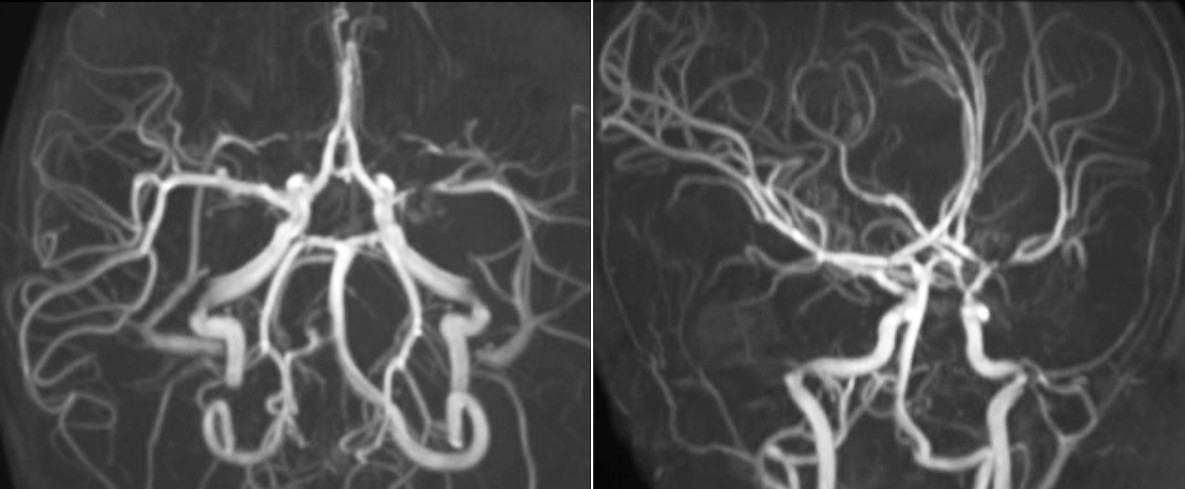

The value of susceptibility weighted imaging in visualizing brain injury is well documented. The Philips multi-echo SWIp technique provides fast susceptibility weighted imaging with enhanced susceptibility contrast and high resolution.

“SWIp helps us identify blood or blood products, calcification, and diseases that affect the vascular system,” says Dr. Miller. “In children with traumatic brain injuries, it highlights areas that are injured, better than some of the previous techniques that we were using. These children often have micro-injuries that cause small amounts of blood or tissue damage. Adding SWIp helps us to better characterize the extent and nature of the injury. Having characterized an injury to the extent of what’s possible supports our diagnostic confidence.”

“I would definitely recommend other users to implement SWIp. We initially added the SWIp sequence following a lot of support for its utility in the literature. Then we directly compared SWIp to the 2D gradient echo sequences that we were using. After a good amount of clinical experience in seeing its benefits, we were confident to replace the old sequences with SWIp. It gives us a better assessment of the physiological processes of the brain that were less apparent on our previous imaging sequences,” says Dr. Miller. “SWIp is now a routine sequence for imaging traumatic brain injury patients at PCH, and it’s episodically added for patients who have intracranial vascular abnormalities.”

“I believe SWIp is rapidly becoming the standard in imaging traumatic brain injury, because of its high sensitivity to venous blood products. SWIp may even help attract patients; our neurosurgeons often ask to have the patients imaged on our scanners with highly sensitive techniques like SWIp. There’s also a growing application of SWI sequences in other vascular abnormalities because of the possibilities around physiological assessment of the brain than just a standard structural imaging.”